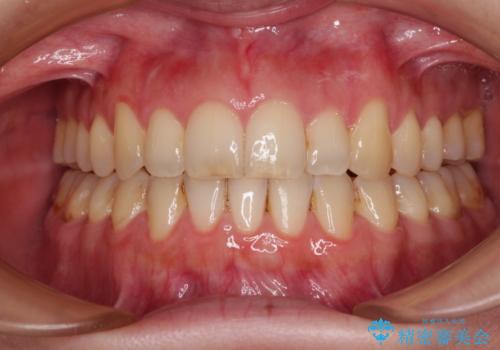

- 口元の突出感と口の閉じにくさを気にして来院された患者様です。

上下左右第一小臼歯4本を抜歯し、ワイヤー装置にて口元を引っ込めるよう矯正治療を行うこととしました。

2年~2年半が治療期間の目安でしたが、順調に治療が進み、1年9か月で満足のいく歯列となりました。